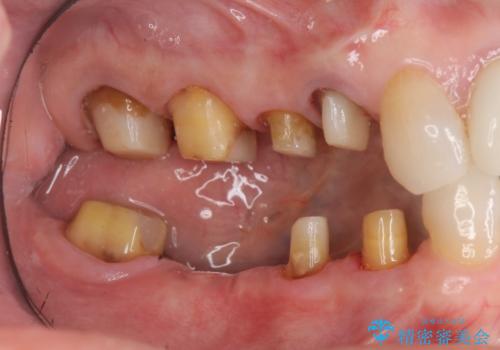

臼歯部メタルフリー再補綴

- 治療してからの年月が経過し、かみにくくなったブリッジ・クラウンを全てやりかえたいと希望され来院されました。

クラウン・ブリッジを作り替えるにあたり虫歯の徹底的な除去・根管治療のやり直しを行い今後やり直しをしなくて済むような環境を整えていきます。

装着して長期間経過したブリッジやクラウンは隙間から細菌が侵入し虫歯が再発してしまっていることがあります。

長期的に問題のないブリッジ・クラウンを作製するため、虫歯をしっかりと除去すること精密な根管治療を行うことが肝要です。